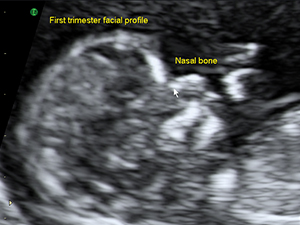

Facial profile in the first trimester